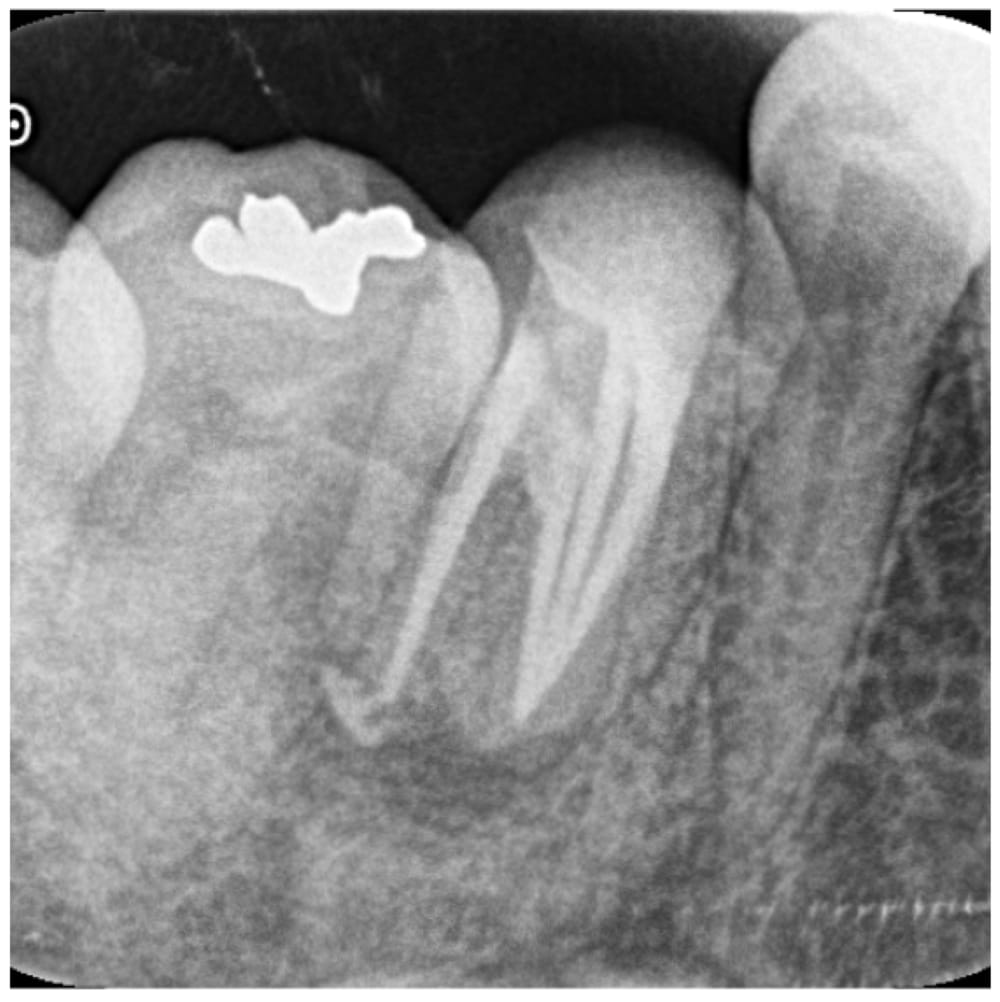

根の先の膿が大きく、歯茎も腫れている状態でした。過去の根管治療ではラバーダムは使用されておらず、根管充填の質もPoorであることから、再根管治療を行うことになりました。

根管は4根管があり、過去の充填材料を除去する必要がある点、根管内の感染が強い点から、根管貼薬を行う2回法で処置を行いました。治療は問題なく完了しましたが、残存歯質量に不安があり、長期予後はQuestionableな状態でした。レジンにてコア築造を行い、6ヶ月後の経過観察となりました。